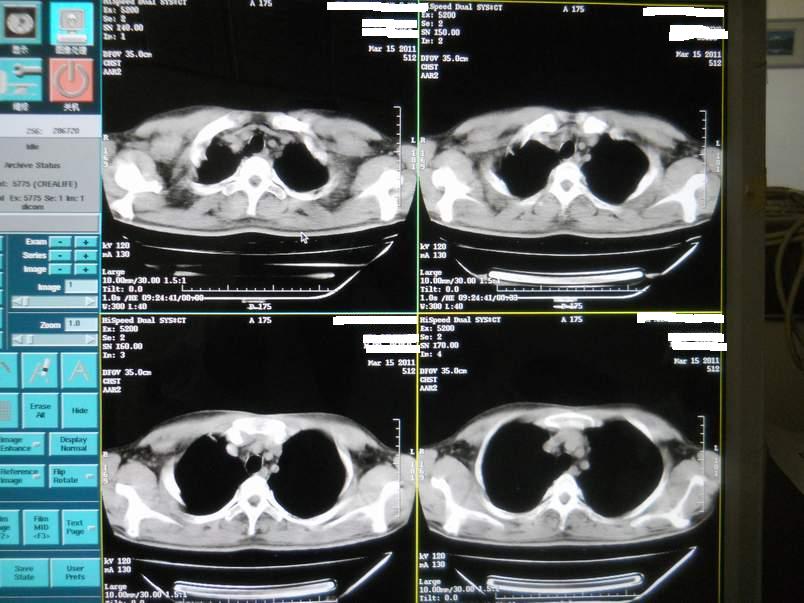

肺霉菌感染

男,22岁,一年前诊断马尔菲尼青霉菌感染,多次复查CT。多次HIV阴性。最近两次CT图片。有实验室结果。

最近实验室检查结果:霉菌感染。